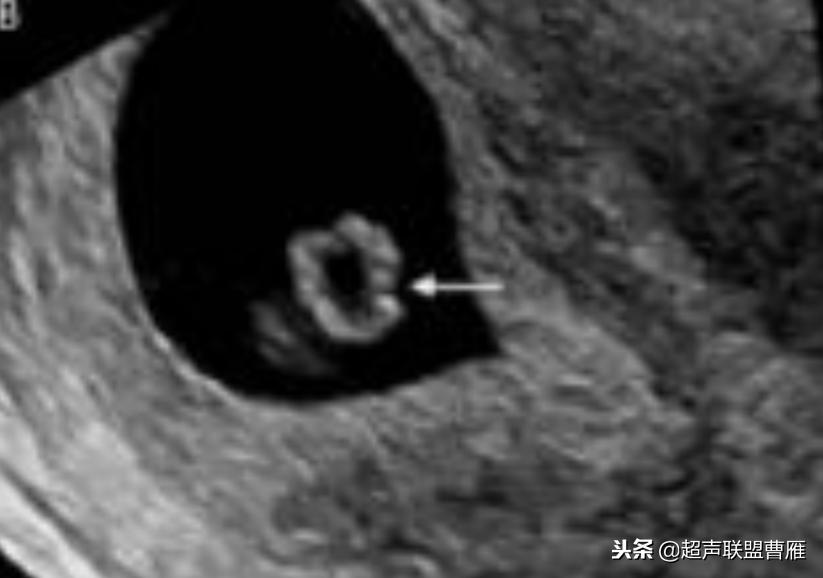

· 正常情况下,卵黄囊中央表现为无回声,周边为厚薄均一、边界清晰的环形高回声。

· 正常卵黄囊内径一般在3-5mm,妊娠第5-10周逐渐增大,而10周后逐渐减小,一般12周前消失。

正常早孕卵黄囊声像图

早孕 胚芽 卵黄囊

5周+ 、6周+ 声像图